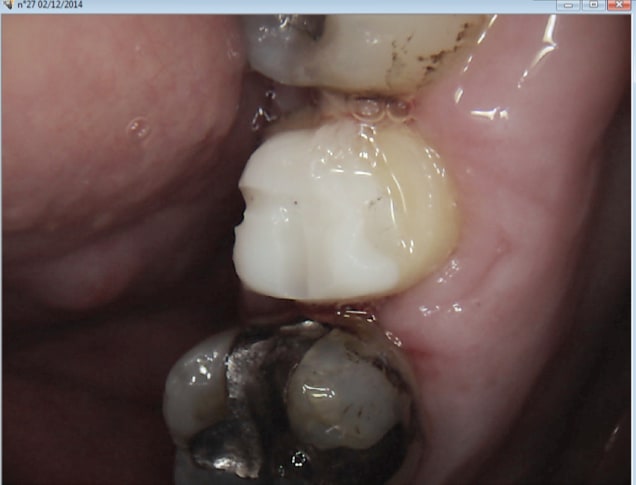

Ca c'est un ic coiffe protilab, pourquoi ca a merdé au bout de 7 ans à ton avis ? -)

parce que le pivot ne va pas a l'apex

pas de pivot jusqu'a l'apex

ben ouais c'est pas la couronne qui a merdé. Je peux en parler car le patient c'est moi. C'est le cas dans 98 % des cas. -)

Par contre l'inlay core tout ceram ca a été une vraie merde à virer il n'était pas près de se barrer crois moi ! . -)